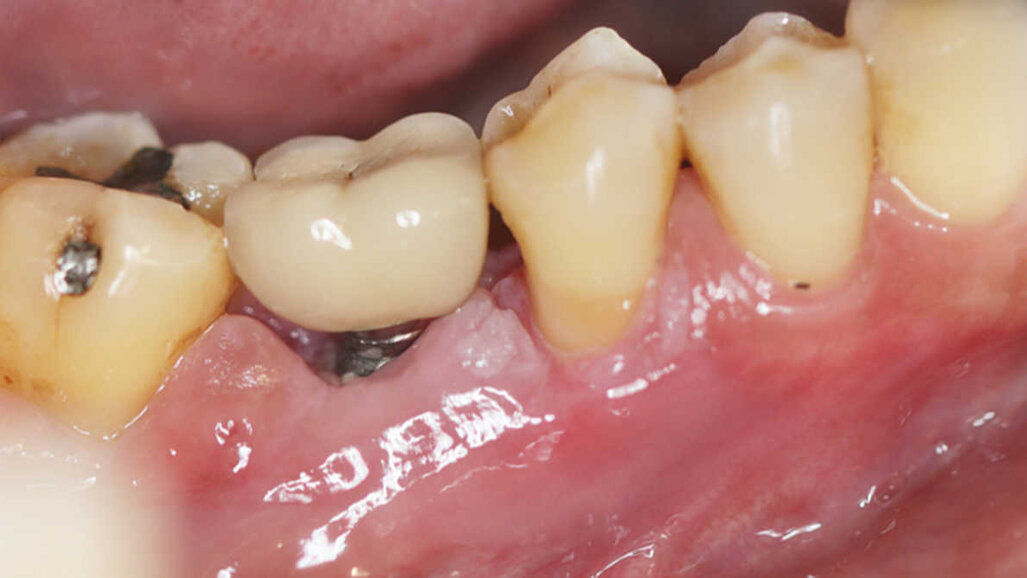

Od ovih 596 pacijenata, 42 % zahvatila je barem jedna biološka ili tehnička komplikacija tijekom razdoblja praćenja. Ustanovljeno je da su tehničke komplikacije najčešće, pri čemu je jedna četvrtina pacijenata doživjela ovu vrstu komplikacija. Najčešće tehničke komplikacije bile su lom obložne keramike (11,0 %), zatim otpuštanje vijaka (9,1 %) i odcementiravanje (5,9 %). Lomovi implantata ili implantatnih nadogradnji uočeni su rijetko.Karlsson je odredila opseg restaurativne terapije kao najjači pokazatelj rizika za tehničke komplikacije.

Kao druga najčešća komplikacija zabilježen je periimplantitis (19,0 %). Liječenje bolesti samo nekirurškim metodama, u vidu stručnog čišćenja i uputa o oralnoj higijeni, pokazalo se nedostatnim. Dodatno kirurško liječenje, međutim, moglo je spriječiti daljnje napredovanje.Gubitak implantata, koji je zabilježen kod 8 % sudionika, rezultirao je najvećim ukupnim troškom (2403 USD/2012 EUR), a zatim slijede kombinacije različitih komplikacija (2347 USD). Trošak tehničkih komplikacija i periimplantitisa bio je sličan s 1614 USD i 1619 USD.U sveučilišnom priopćenju za tisak, Karlsson je komentirala nalaze istraživanja: "Rezultati pružaju stomatološkim stručnjacima i pacijentima važne informacije, omogućujući im da procijene i smanje rizik od komplikacija povezanih s implantoprotetskom terapijom."